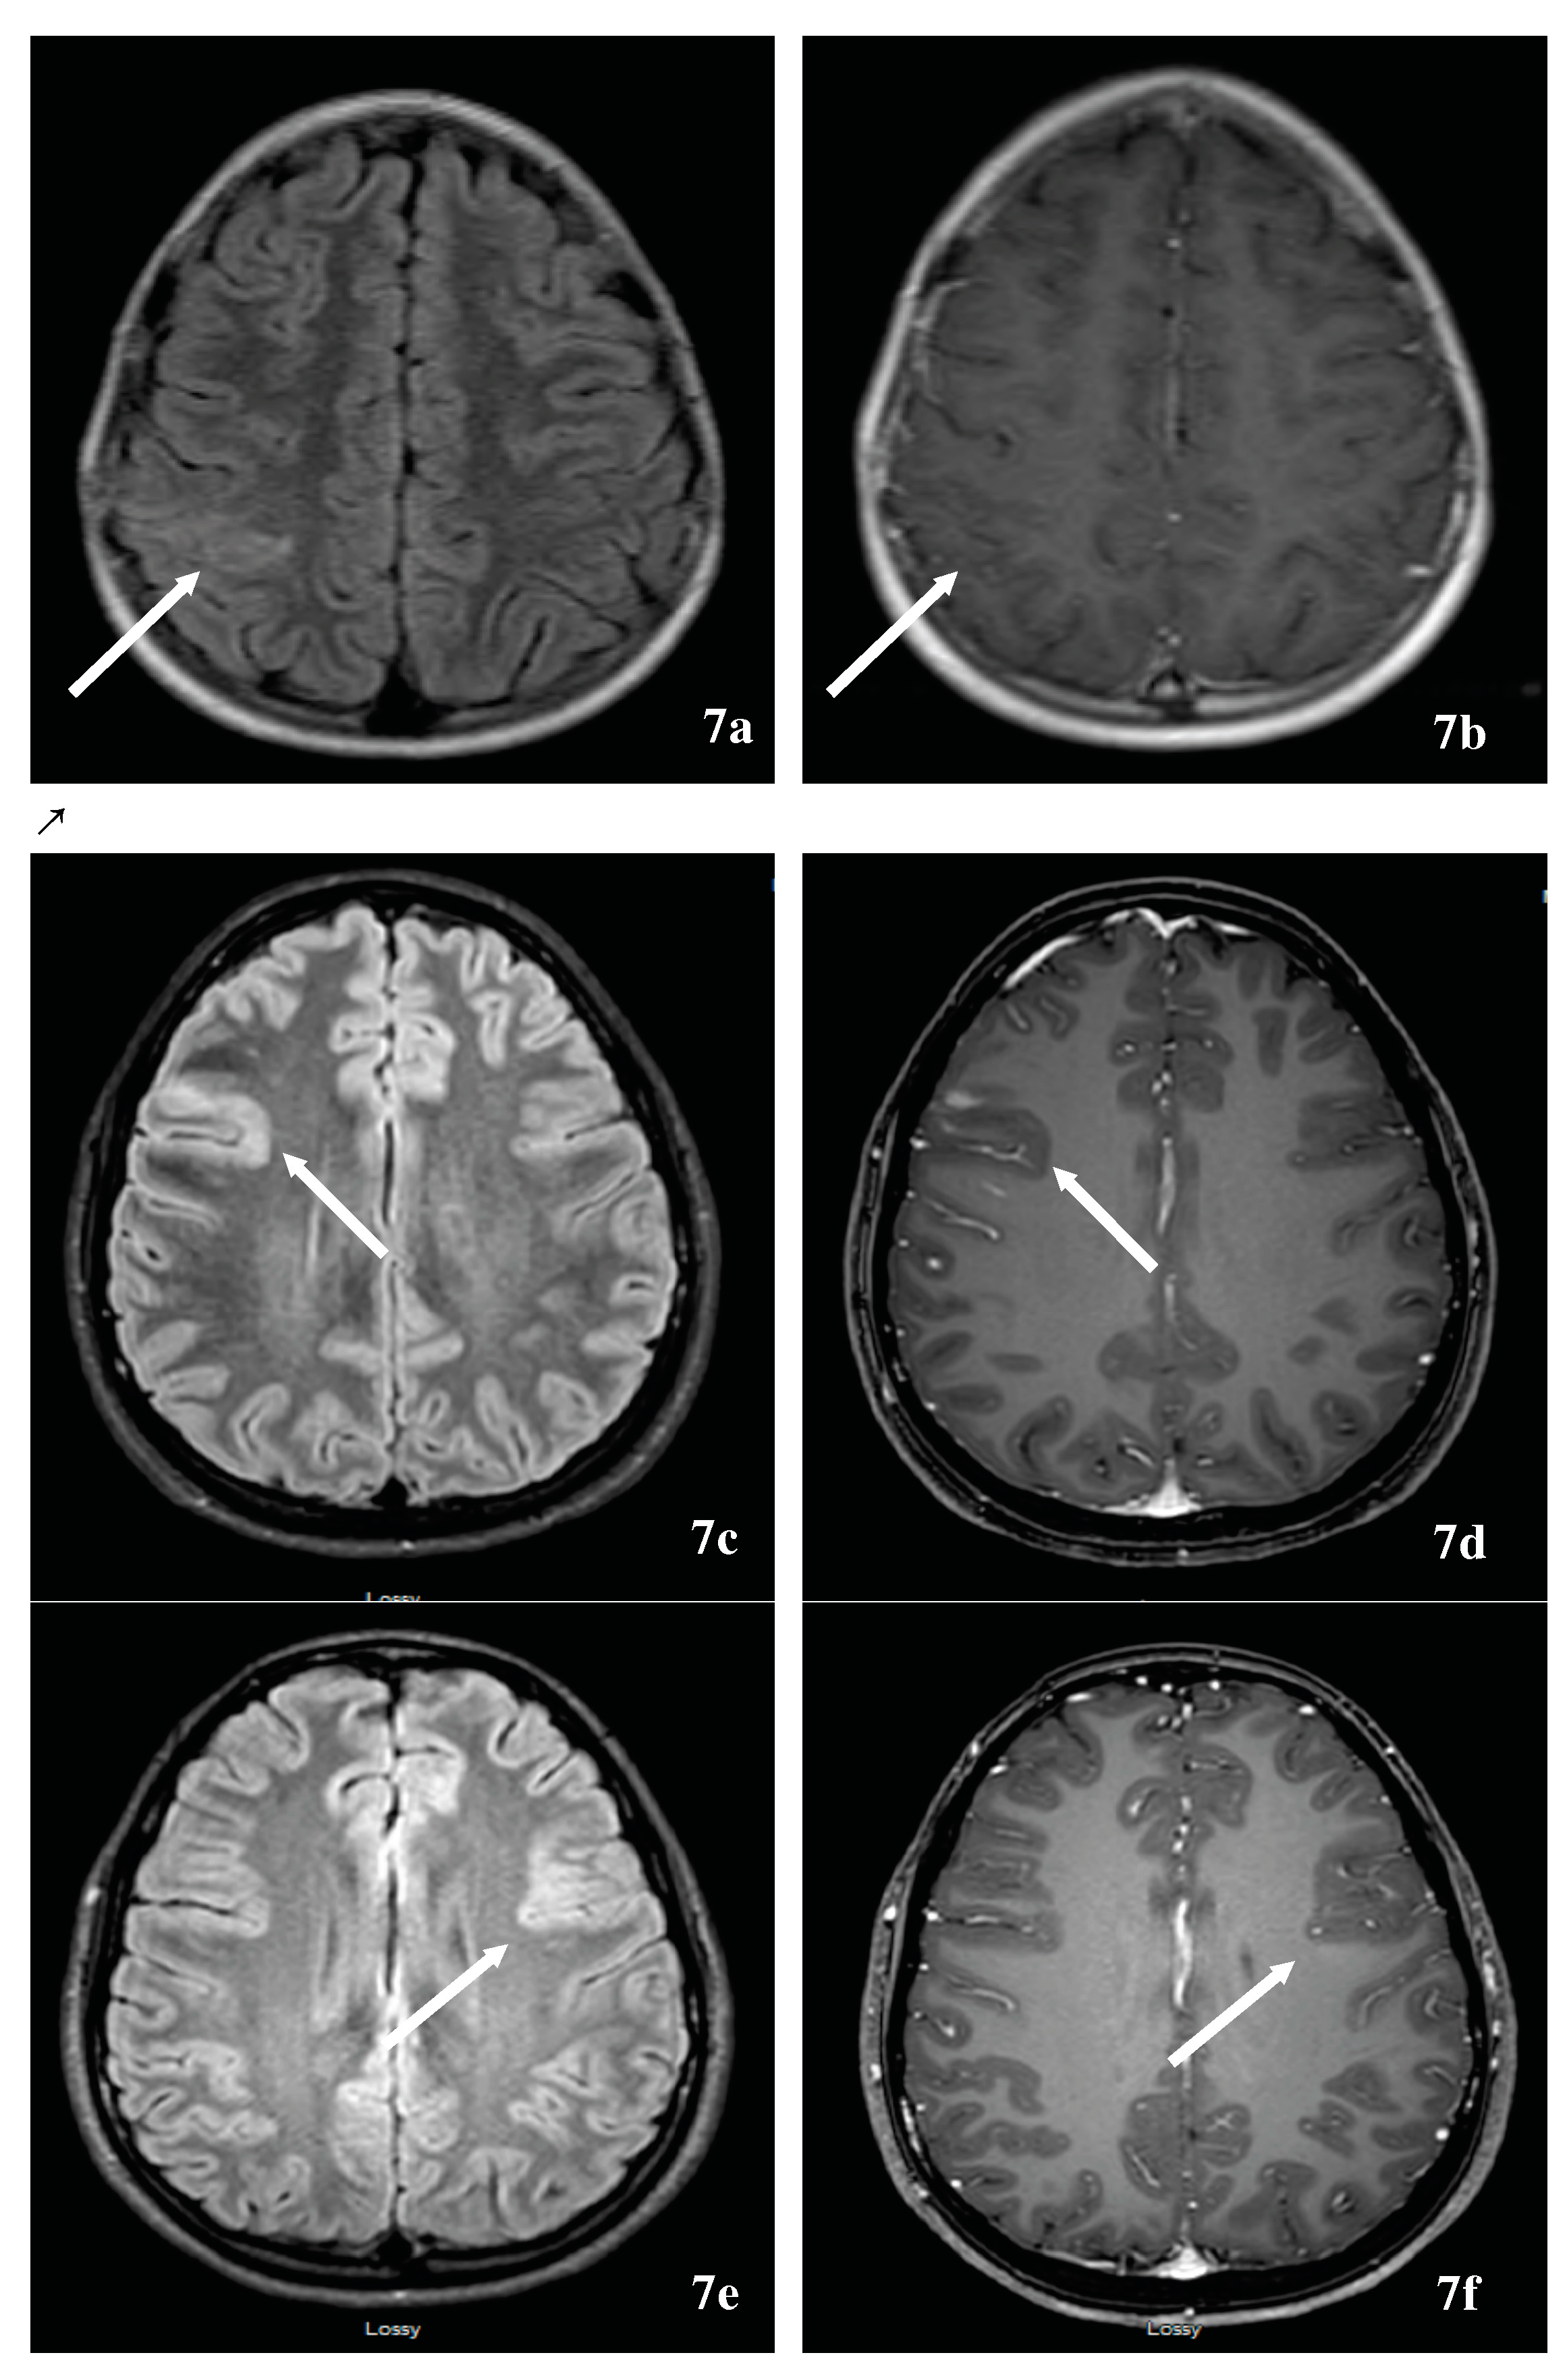

- Cheng, C.; Jiang, Y.; Chen, X.; Dai, Y.; Kang, Z.; Lu, Z.; Peng, F.; Hu, X. Clinical, radiographic characteristics and immunomodulating changes in neuromyelitis optica with extensive brain lesions. BMC Neurol. 2013, 13, 72. [Google Scholar] [CrossRef] [PubMed]

- Saiki, S.; Ueno, Y.; Moritani, T.; Sato, T.; Sekine, T.; Kawajiri, S.; Adachi, S.; Yokoyama, K.; Tomizawa, Y.; Motoi, Y.; et al. Extensive hemispheric lesions with radiological evidence of blood-brain barrier integrity in a patient with neuromyelitis optica. J. Neurol. Sci. 2009, 284, 217–219. [Google Scholar] [CrossRef] [PubMed]

- Roy, U.; Saini, D.S.; Pan, K.; Pandit, A.; Ganguly, G.; Panwar, A. Neuromyelitis Optica Spectrum Disorder with Tumefactive Demyelination mimicking Multiple Sclerosis: A Rare Case. Front. Neurol. 2016, 7, 73. [Google Scholar] [CrossRef] [PubMed]

- Matsushita, T.; Isobe, N.; Matsuoka, T.; Ishizu, T.; Kawano, Y.; Yoshiura, T.; Ohyagi, Y.; Kira, J. Extensive vasogenic edema of anti-aquaporin-4 antibody-related brain lesions. Mult. Scler. 2009, 15, 1113–1117. [Google Scholar] [CrossRef] [PubMed]